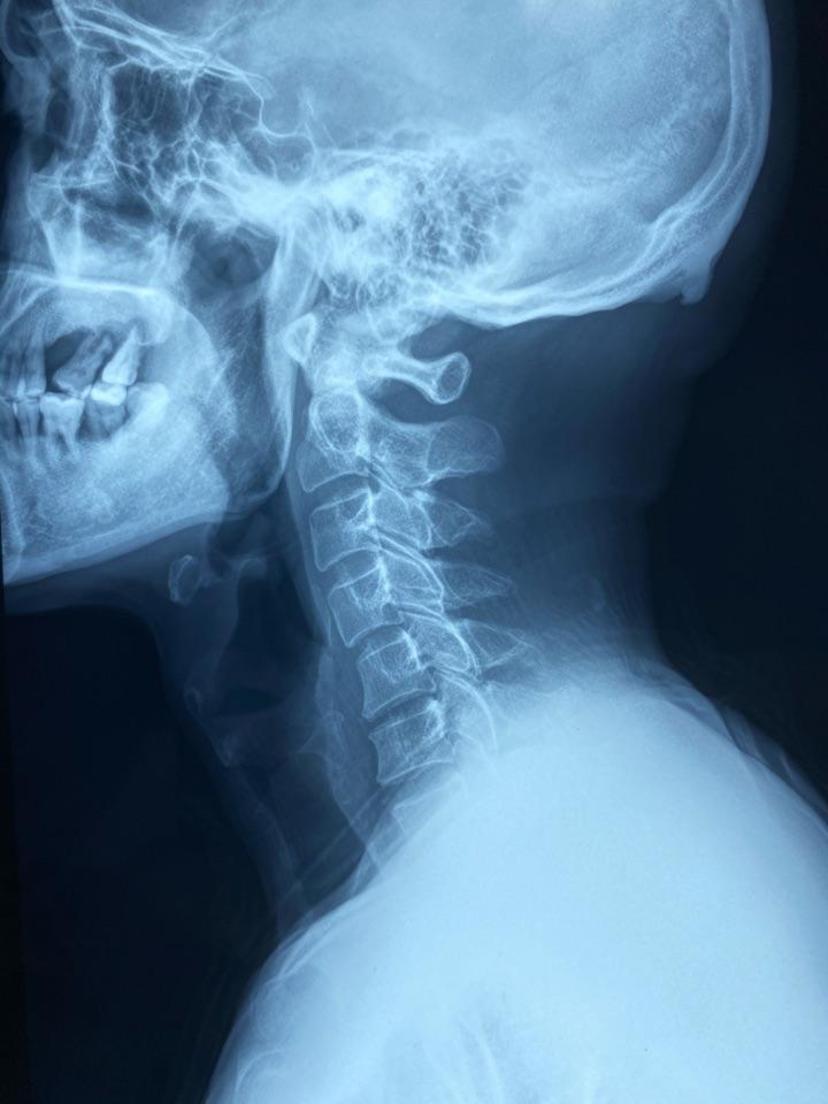

颈椎反弓术中完整取出压迫脊髓神经的椎间盘术后片子位置良好,颈椎

颈椎曲度反弓,该怎么办,谢谢!

"颈椎曲度变直";再严重一点,颈椎向相反方向弯曲,就形成了"颈椎反弓"